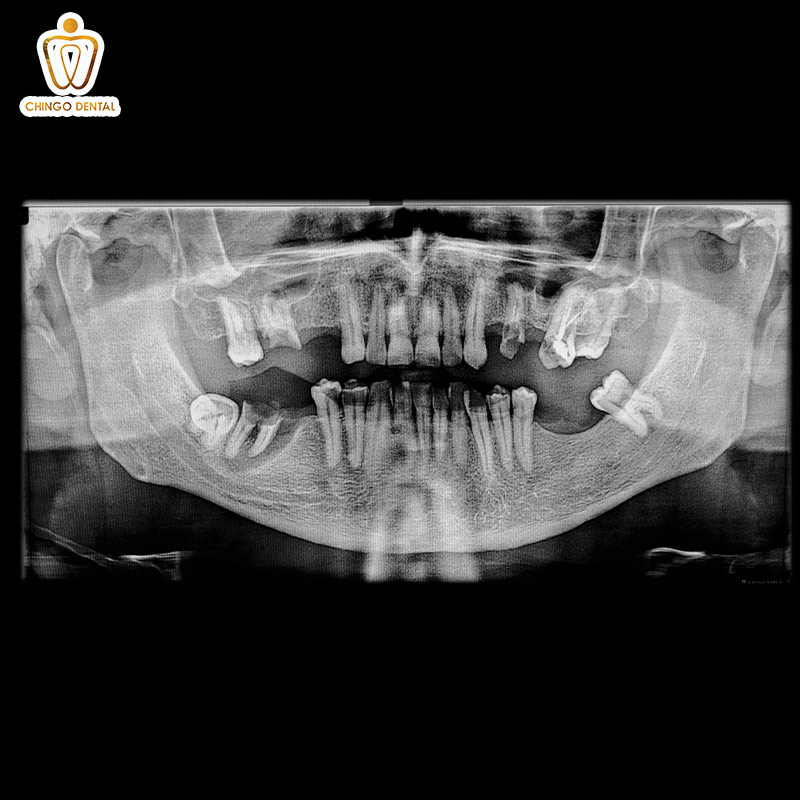

Chính vì sự đa dạng này, việc chụp phim X-quang. Trước khi thực hiện các thủ thuật như nhổ răng hay niềng răng tại Chingo Dental. Là bước bắt buộc để bác sĩ nắm trọn cấu trúc chân răng. Đảm bảo can thiệp an toàn và chính xác tuyệt đối.

Việc có nên nhổ răng số 4 để niềng không, không thể quyết định qua cảm quan thông thường. Một kế hoạch điều trị thông minh phải dựa trên phim chụp X-quang, phim CT Cone Beam. Và sự phân tích tỉ lệ khuôn mặt của từng khách hàng.

Luôn yêu cầu chụp phim 3D: Chỉ có phim chụp chuyên sâu mới hiển thị rõ số chân và ống tủy mà mắt thường không thấy được.

Thực trạng: Khách hàng N.T.H đến với Chingo trong tình trạng răng khấp khểnh nặng, cần nhổ răng số 4 để tạo khoảng trống dàn đều răng. Qua phim chụp X-quang CT Cone Beam 3D, bác sĩ phát hiện chiếc răng số 4 hàm trên của bạn không phải có 2 chân như thông thường mà có tới 3 chân trụ vững chắc.